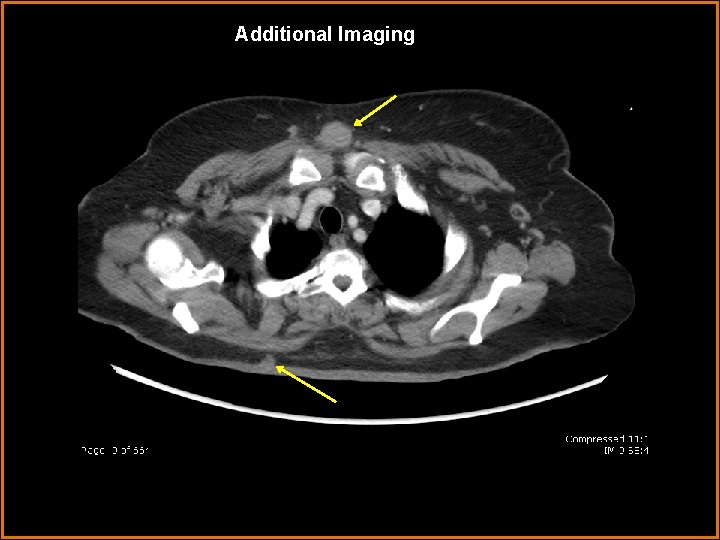

Diagnosis • A biopsy was performed that demonstrated cutaneous lymphoma. Four months later, a CT of the chest, abdomen, and pelvis was perform. This demonstrated multiple cutaneous/subcutaneous nodular lesions.

Additional Imaging